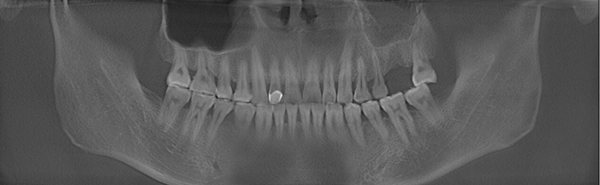

郑先生口腔全景ct拍摄

郑先生口腔内部全景片